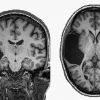

+14 +1She Was Missing a Chunk of Her Brain. It Didn’t Matter

A woman grew up without her left temporal lobe, which highlights how amazingly plastic the brain is. IN EARLY FEBRUARY 2016, after reading an article featuring a couple of scientists at the Massachusetts Institute of Technology who were studying how the brain reacts to music, a woman felt inclined to email them. “I have an interesting brain,” she told them.